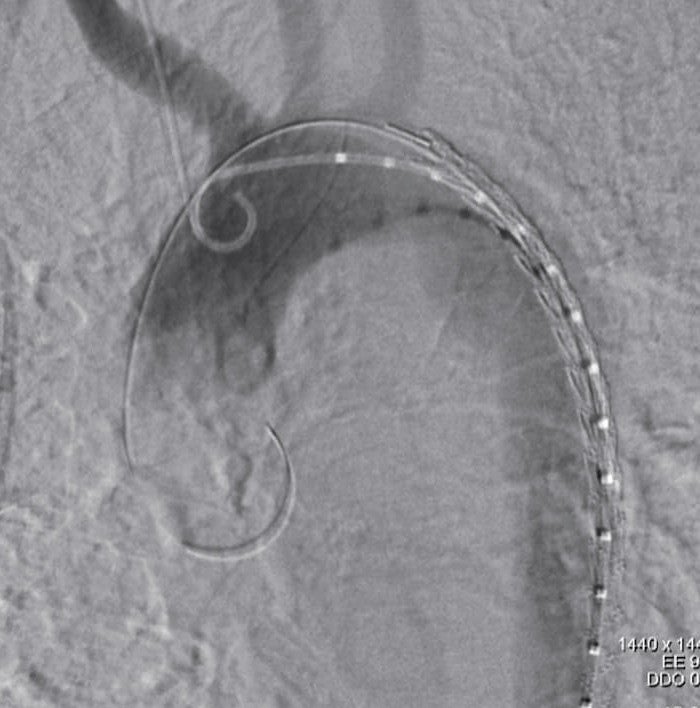

輸血で血圧を維持しつつ全身麻酔にて右鼠径部を切開し総大腿動脈を露出した。ヘパリンを投与したのち8 Frのシースを挿入、ここから注意深くピッグテールカテーテルと血管造影用ガイドワイヤーを上行大動脈まで挿入し、スティッフガイドワイヤーに入れ替えたのち、シースをゴア®ドライシール フレックス イントロデューサシース20 Frに入れ替えた。TAG®コンフォーマブル ステントグラフト アクティブコントロールシステムTGM282815Jを弓部大動脈まで挿入、造影用pigtailカテーテルを上行大動脈まで挿入ののち、LAO45度にてDSAを撮影し、左鎖骨下動脈および大動脈損傷部の位置関係を確認し、マーキングした。ステントグラフトの展開はスティッフガイドワイヤーにて大弯にステントグラフトを押し付けた状態で、中枢端のパーシャルアンカバードステントがわずかに左鎖骨下動脈にかかる程度に固定し展開した。最後にangulation controlを使用し小弯側を十分に圧着させて展開終了とした。DSAにて明らかなエンドリークのないことを確認した。また、展開後は不安定であった血圧も安定した。デリバリーシステムを回収し、右総大腿動脈を修復し、プロタミン投与ののち閉創した。手術時間は58分であり、当院搬入からステント挿入まで約130分であった。

TAG®コンフォーマブル ステントグラフト アクティブコントロールシステムは外傷に対して適応となる唯一のデバイス*であり、構造的に比較的短い中枢ランディングでもシーリング効果を発揮するよう設計されている。更に、本症例ではangulation controlを用いることにより弓部小弯側の大動脈壁にステントグラフトを密着させることができ、エンドリークは生じなかった。外傷性大動脈損傷症例は中枢ランディングが短く、弓部の角度が急峻であることが多いため、小弯側ランディングが問題になるが、アクティブコントロールシステムにより従来以上にエンドリークを抑制するための機能が追加されたことで、外傷性大動脈損傷に対して更に効果を発揮できることとなったと言える。